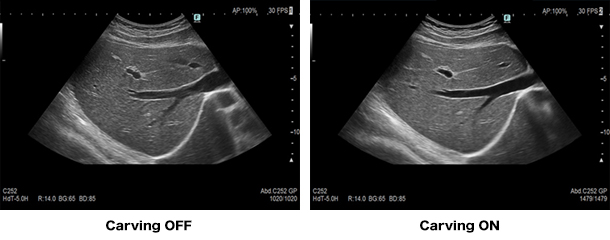

「見やすい」画像を提供する「Carving Imaging」

組織構造の視認性を追及した「見やすい」画像を実現しました。被検者依存の少ない安定した描出を実現します。